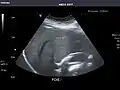

Renal ultrasonography

Ultrasound scan of a kidney (right side)

Ultrasonography of the kidneys is essential in the diagnosis and management of kidney-related diseases. The kidneys are easily examined, and most pathological changes in the kidneys are distinguishable with ultrasound.[7]